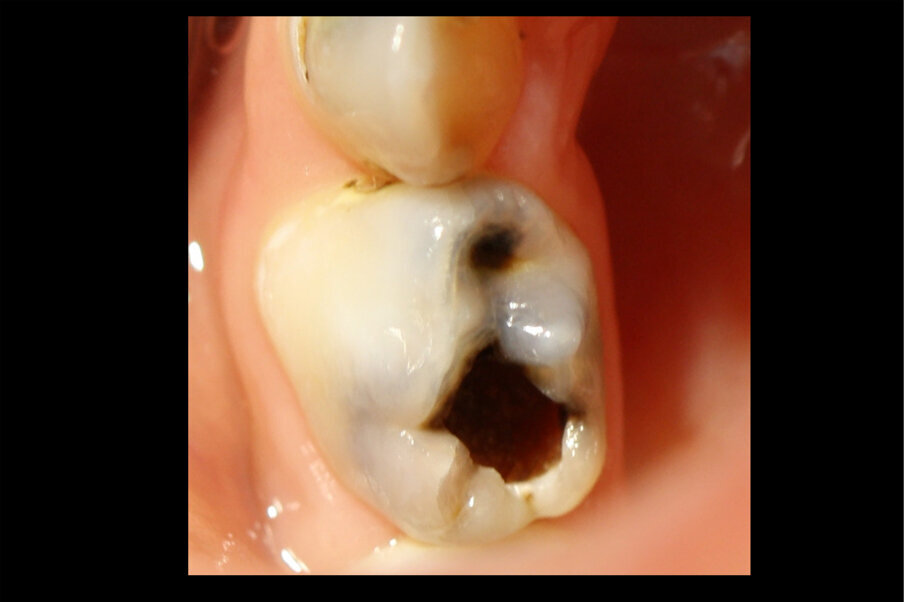

Afbeelding 3. Casus 2: 29-09-17. Eerste bezoek. Actieve cariës-instructies en ZDF aangebracht.

Afbeelding 4. Casus 2: 09-02-18. Tweede bezoek. Na 4 maanden klachtenvrij.

Afbeelding 5. Casus 2: 25-05-18. De caviteit in 74 blijkt niet goed reinigbaar, daarom Fuji Triage geplaatst.

Afbeelding 6. Casus 2: 18-10-18. Fuji Triage ‘noodvulling’ voldoet na 5 maanden.